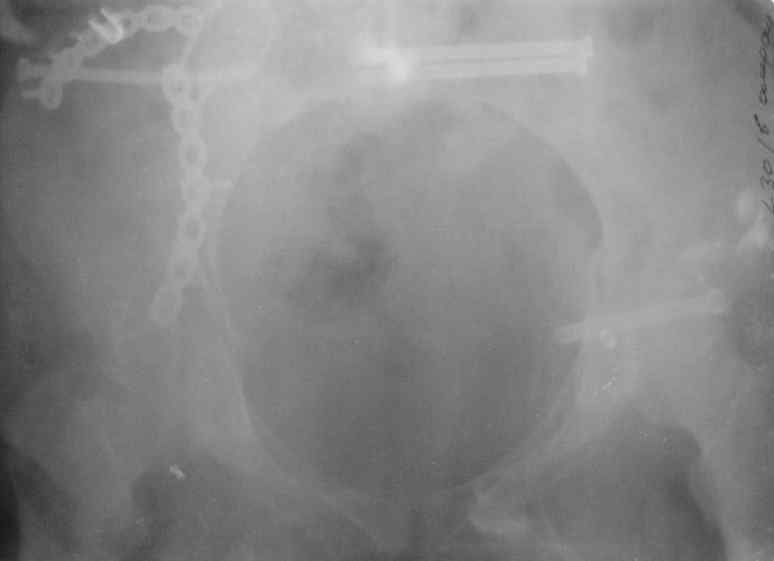

Здравствуйте, коллеги. Какие будут мнения по поводу лечения представляемой больной?

Молодая девушка 19 лет, травма 1 год назад, тогда же прооперирована.

В настоящее время имеются ноющие боли в области крестца слева, нарушение походки, ощущение неуверенности, слабости в левой нижней конечности, неврологически -непостоянные парестезии в левой нижней конечности. Ходит с дополнительной опорой, страдает от ожирения.

В приложении снимки при поступлении и послеоперационные год назад.